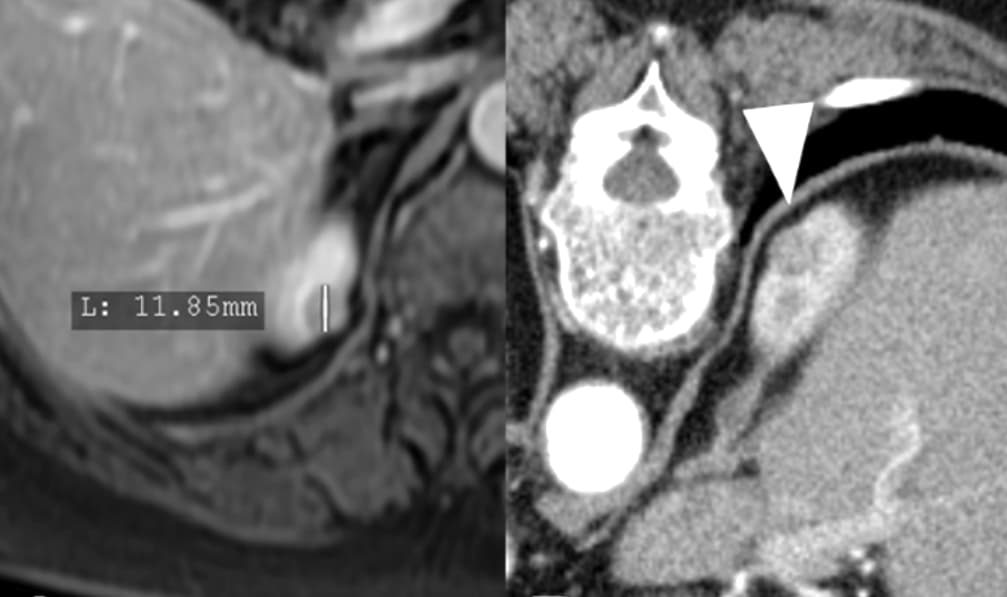

Une vaste étude danoise montre qu’une procédure mini-invasive d’ablation est aussi efficace que la chirurgie pour traiter les petits cancers du rein, avec une récupération plus rapide et moins de complications. Les résultats de l’étude ont été publiés récemment dans la Revue Radiology.